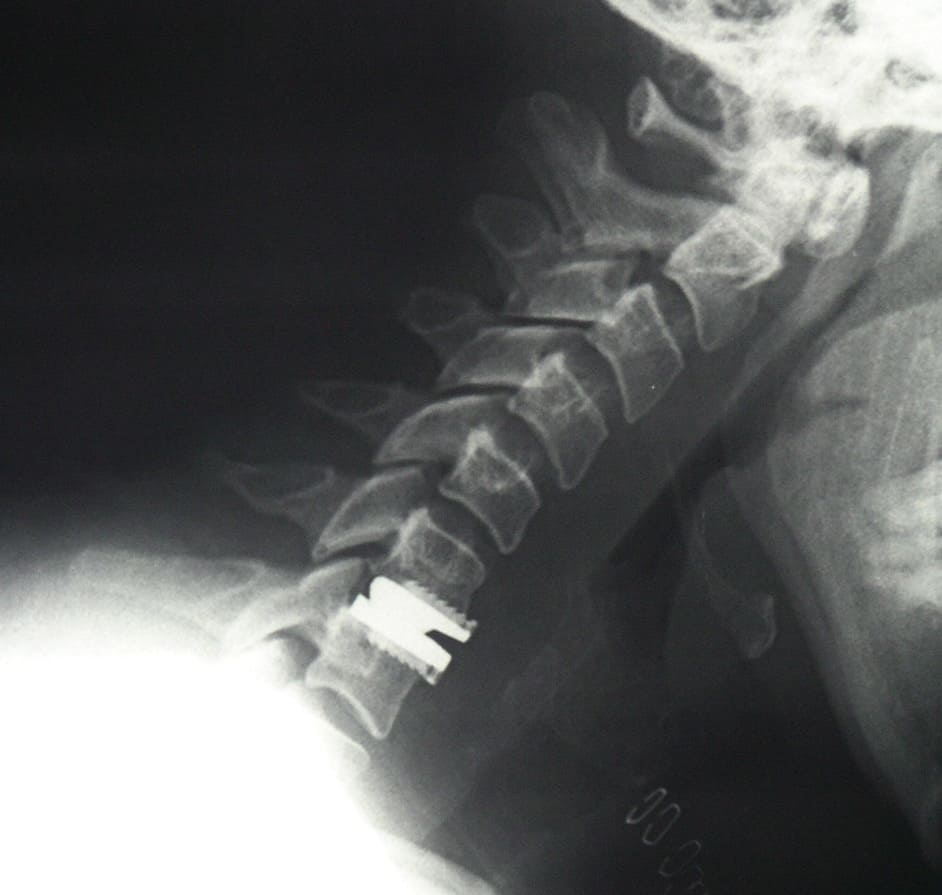

Cuando se trata de aliviar la presión sobre un nervio y el dolor de cuello, la cirugía usualmente incluye una extracción completa del disco o discectomía, seguido por el implante de un dispositivo espaciador o una prótesis total de disco. Esta cirugía se hace en la parte anterior del cuello (se le llama microdiscectomía y artrodesis o prótesis discal anterior). Afortunadamente, estos procedimientos muchas veces pueden realizarse usando técnicas de invasión mínima. La cirugía de invasión mínima no requiere incisiones grandes, sino que hace pequeños cortes y usa instrumentos y dispositivos minúsculos especializados durante la operación, como un microscopio y un endoscopio.